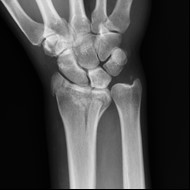

Na obrazie radiologicznym nadgarstka uwidoczniono złamanie nasady

A. dalszej kości promieniowej.

B. bliższej kości promieniowej.

C. bliższej kości łokciowej.

D. dalszej kości łokciowej.